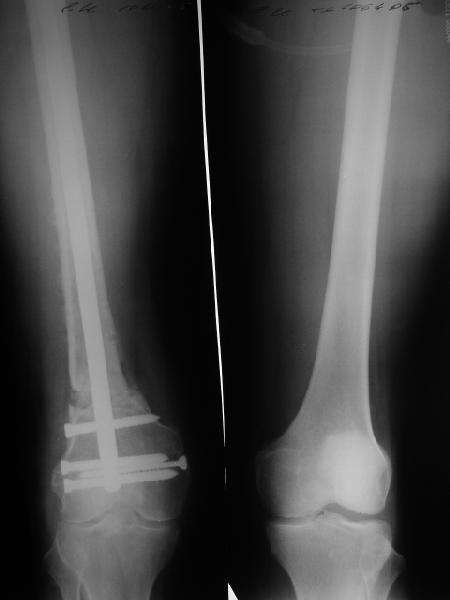

В приложении пример, как их использовали после остеотомии бедра по поводу сросшегося с вальгусом перелома, чтобы не дать гвоздю уйти во внутренний мыщелок.

Сейчас Poller спицы мы зачастую вводим сразу после обработки сегмента, еще до разреза и введения штифта, это не отнимает много времени. А углы иной раз бывают без них ой какие заметные.